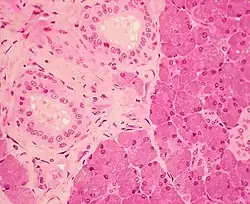

Stratified cuboidal epithelium in the ducts of the parotid gland, visible as the borders of the two circular structures in the upper left. | |

Stratified cuboidal epithelium, highlighting the nucleuses, the rest of the epithelial cells, and underlying connective tissue.

Stratified cuboidal epithelium is a type of epithelial tissue composed of multiple layers of cube-shaped cells. Only the most superficial layer is made up of cuboidal cells, and the other layers can be cells of other types. Topmost layer of skin epidermis in frogs, fish is made up of living cuboidal cells.

This type of tissue can be observed in sweat glands, mammary glands, circumanal glands, and salivary glands.[1][2] They protect areas such as the ducts of sweat glands,[3] mammary glands, and salivary glands. They are also observed in the linings of urethra.